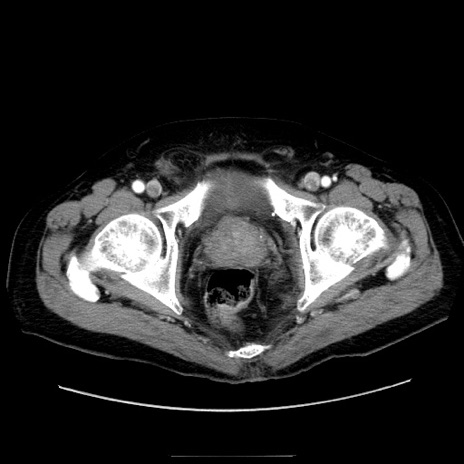

冠状断像